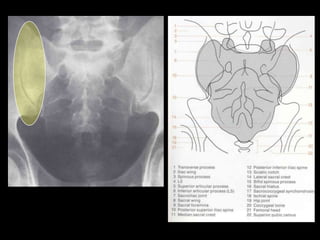

This document provides an overview of normal musculoskeletal imaging. It discusses basic x-ray concepts and densities. It then reviews normal anatomy as seen on x-rays of the skull, spine, pelvis, chest, and extremities. Key anatomical structures are labeled on example x-rays for the shoulder, hip, knee, and foot. Quizzes are included to test recognition of anatomical structures and patient age based on x-rays.